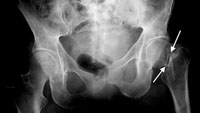

Intertrochanteric Fracture. This occurs further down the bone and tends to have better blood supply to the fracture pieces.

Stable Impacted Fracture. Certain fractures that have not moved ("displaced") may not require surgery. Because there is a risk that they may move later on, they are often fixed.